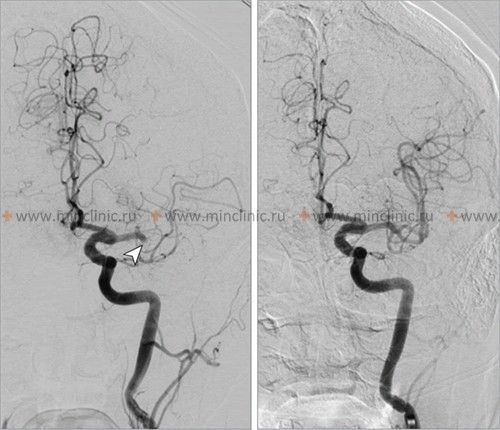

თუ ეჭვია ცერებრული არტერიის ემბოლიაზე, არტერიული ოკლუზიის ადგილმდებარეობის იდენტიფიცირება და ქვემოთმდებარე ტვინის ქსოვილის შეფასება კრიტიკულია მწვავე მკურნალობის (როგორიცაა თრომბექტომია) დასაგეგმად [16, 19]. არაინვაზიური სისხლძარღვოვანი ვიზუალიზაცია, როგორიცაა კტ ანგიოგრაფია (CTA) ან მრ ანგიოგრაფია (MRA), ჩვეულებრივ ტარდება გადაუდებლად [16]. კონვენციური კათეტერზე დაფუძნებული ცერებრული ანგიოგრაფია (ციფრული სუბტრაქციული ანგიოგრაფია - DSA) უზრუნველყოფს სისხლძარღვების უმაღლესი რეზოლუციის დეტალებს, მაგრამ არის ინვაზიური [14]. ის შეიძლება ჩატარდეს, თუ იგეგმება ენდოვასკულური მკურნალობა (თრომბექტომია) ან თუ არაინვაზიური ვიზუალიზაცია არასაკმარისად ინფორმატიულია [16, 19]. მნიშვნელოვანია აღინიშნოს, რომ რამდენიმე საათის ან დღის შემდეგ, ემბოლმა შეიძლება მიგრირება განიცადოს დისტალურად, ფრაგმენტაცია ან სპონტანური ლიზისი (დაშლა), რაც ნიშნავს, რომ მოგვიანებით ჩატარებულმა ანგიოგრაფიამ შეიძლება არ აჩვენოს თავდაპირველი ოკლუზია, რის გამოც ემბოლიური ინსულტის საბოლოო დიაგნოზი ზოგჯერ სავარაუდოა კლინიკური სურათისა და ინფარქტის პატერნის საფუძველზე [1]. სტანდარტული ინტრავენური კონტრასტის შეყვანა რუტინული კტ ან მრტ სკანირების დროს ზოგადად მოკლებულია იმ რეზოლუციას და დროით სიზუსტეს, რაც აუცილებელია სისხლძარღვებში მცირე ცერებრული ემბოლების უშუალო ვიზუალიზაციისთვის [14].

კლინიკური გამოსავალი დიდად არის დამოკიდებული თავად ემბოლზე და პაციენტის სისხლძარღვოვან ანატომიაზე [1]. ემბოლის ზომა, ლოკაცია და შემადგენლობა (მაგ., კოლტი, ცხიმი, სიმსივნე) განსაზღვრავს, რომელი ცერებრული არტერია დაიხშობა და, შესაბამისად, განვითარებული ცერებრული ინფარქტის (ინსულტის) მასშტაბსა და ლოკაციას [1, 2]. დიდი ემბოლები (მაგ., 2-3 მმ ან მეტი) უფრო მეტად ახშობენ დიდ სისხლძარღვებს, როგორიცაა ტვინის შუა არტერიის (MCA) ღერო, რაც პოტენციურად იწვევს ვრცელ ინფარქტს, რომელიც მოიცავს თავის ტვინის ქერქს, ქვემდებარე თეთრ ნივთიერებას და რუხი ნივთიერების ღრმა სტრუქტურებს (ბაზალური განგლიები, თალამუსი) [1, 2]. უფრო მცირე ემბოლები შეიძლება გადაადგილდეს უფრო შორს დისტალურად, დაახშოს MCA-ის ან ბაზილარული არტერიის მცირე პერფორანტული ტოტები, რაც ხშირად იწვევს უფრო მცირე, ღრმა ინფარქტებს, რომლებიც ცნობილია როგორც ლაკუნური ინფარქტები (თუმცა ლაკუნური ინსულტები უფრო კლასიკურად ასოცირდება მცირე სისხლძარღვთა დაავადებასთან/ლიპოჰიალინოზთან, ვიდრე ემბოლიასთან) [1, 6].

როდესაც გული ცალსახად იდენტიფიცირებულია, როგორც ემბოლიური წყარო, კვლევები მიუთითებენ თავის ტვინში განაწილების გარკვეულ პატერნზე. გულისმიერი ემბოლების დაახლოებით 80% მიდრეკილია გაიჭედოს ტვინის შუა არტერიის აუზში (რადგან ის იღებს საძილე არტერიის სისხლის ნაკადის ყველაზე დიდ ნაწილს), დაახლოებით 10-11% შეიძლება გადაადგილდეს ტვინის უკანა არტერიის აუზში (უკანა ცირკულაციის მეშვეობით), ხოლო დანარჩენი ნაწილდება ტვინის წინა არტერიის აუზში ან უშუალოდ ხერხემლის ან ბაზილარულ არტერიებში ან მათ ტოტებში [1, 2].